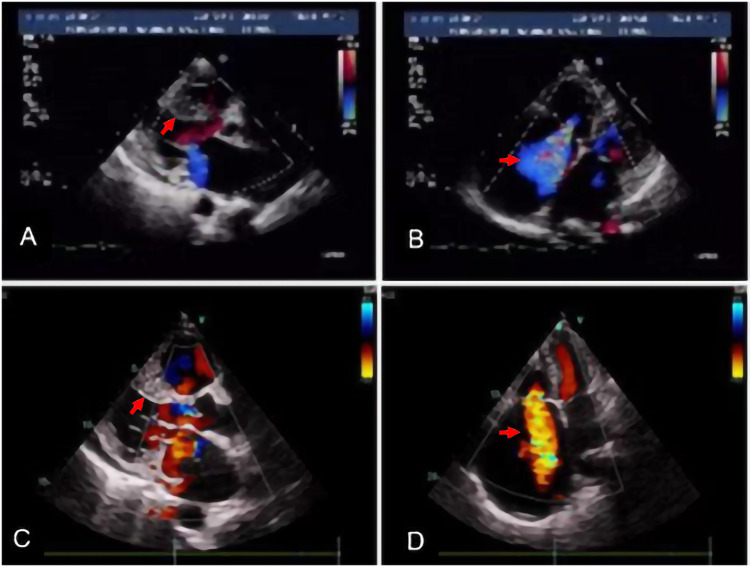

Case presentation: Herein, we present a case study of an individual diagnosed with HCM utilizing next-generation sequencing (NGS). Over the disease course, the patient with hypertrophic cardiomyopathy also presented with sustained atrial fibrillation, characterized by progressive right ventricular dysfunction, resulting in the development of peripheral edema and ascites.